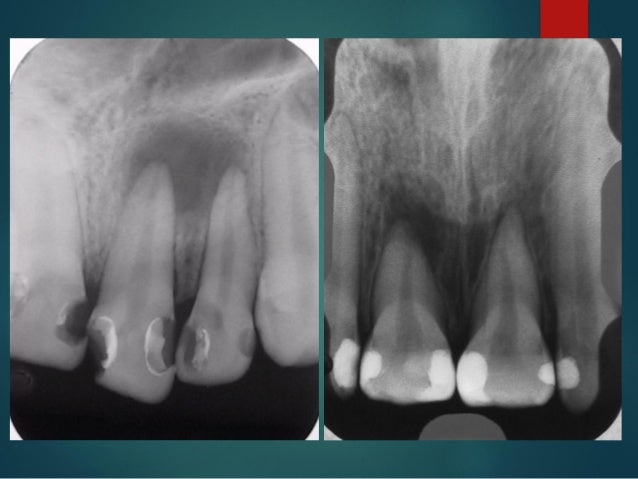

Preventing Recurrent Dental Caries Dental Economics Aquí se muestran los tres tipos de caries.

Tipos De Caries Segun El Tejido Afectado The use of caries detector dye is often frowned upon by the masses.